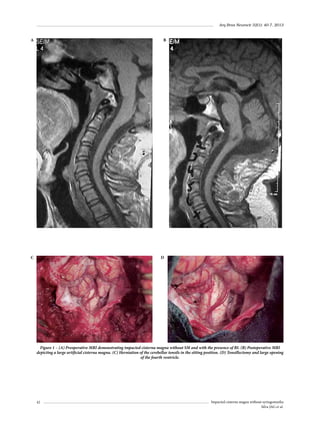

Tew J, et al. Early surgical treatment for supratentorial

intracerebral hemorrhage: a randomized feasibility study.

Stroke. 1999;30(9):1833-9.

Morgenstern LB, Demchuk AM, Kim DH, Frankowski RF,

Grotta JC. Rebleeding leads to poor outcome in ultraearly craniotomy for intracerebral hemorrhage. Neurology.

2001;56(10):1294-9.

Nagasaka T, Tsugeno M, Ikeda H, Okamoto T, Takagawa

Y, Inao S, et al. Balanced irrigation-suction technique with

a multifunctional suction cannula and its application for

intraoperative hemorrhage in endoscopic evacuation of

intracerebral hematomas: technical note. Neurosurgery.

2009;65(4):E826-7.

Longatti P, Fiorindi A, Martinuzzi A. Neuroendoscopic

aspiration of hematocephalus totalis: technical note.

Neurosurgery. 2005;57(Suppl 4):E409.

Yadav YR, Mukerji G, Shenoy R, Basoor A, Jain G, Nelson

A. Endoscopic management of hypertensive intraventricular

haemorrhage with obstructive hydrocephalus. BMC Neurol.

2007;7:1.

Anzai K, Kamiyama K, Sasaki T, Nakamura H. Endoscopic

evacuation of intraventricular hematoma and third

ventriculostomy. No Shinkei Geka. 2000;28(7):599-605.

Barbagallo GM, Platania N, Schonauer C. Long-term

resolution of acute, obstructive, triventricular hydrocephalus

by endoscopic removal of a third ventricular hematoma

without third ventriculostomy. Case report and review of

the literature. J Neurosurg. 2005;102(5):930-4.

Mendelow AD, Gregson BA, Fernandes HM, Murray GD,

Teasdale GM, Hope DT, et al. STICH investigators. Early

surgery versus initial conservative treatment in patients with

spontaneous supratentorial intracerebral haematomas in

the International Surgical Trial in Intracerebral Haemorrhage

(STICH): a randomised trial. Lancet. 2005;365(9457):387-97.

Nagasaka T, Inao S, Ikeda H, Tsugeno M, Okamoto T.

Inflation-deflation method for endoscopic evacuation

of intracerebral haematoma. Acta Neurochir (Wien).

2008;150(7):685-90.

Nieuwkamp DJ, De Gans K, Rinkel GJ, Algra A. Treatment

and outcome of severe intraventricular extension in patients

20.

21.

22.

23.

24.

25.

26.

with subarachnoid or intracerebral hemorrhage: a systematic

review of the literature. J Neurol. 2000;247(2):117-21.

Nyquist P, LeDroux S, Geocadin R. Thrombolytics in

intraventricular hemorrhage. Curr Neurol Neurosci Rep.

2007;7(6):522-8.

Pantazis G, Tsitsopoulos P, Mihas C, Katsiva V, Stavrianos

V, Zymaris S. Early surgical treatment vs conservative

management for spontaneous supratentorial intracerebral

hematomas: a prospective randomized study. Surg Neurol.

2006;66(5):492-501.

Nagasaka T, Tsugeno M, Ikeda H, Okamoto T, Inao S,

Wakabayashi T. Early recovery and better evacuation rate

in neuroendoscopic surgery for spontaneous intracerebral

hemorrhage using a multifunctional cannula: preliminary

study in comparison with craniotomy. J Stroke Cerebrovasc

Dis. 2011;20(3):208-13.

Nakano T, Ohkuma H, Ebina K, Suzuki S. Neuroendoscopic

surgery for intracerebral haemorrhage – comparison

with traditional therapies. Minim Invasive Neurosurg.

2003;46(5):278-83.

Nishihara T, Teraoka A, Morita A, Ueki K, Takai K, Kirino T.

A transparent sheath for endoscopic surgery and its

application in surgical evacuation of spontaneous

intracerebral hematomas. Technical note. J Neurosurg.

2000;92(6):1053-5.

Zuo Y, Cheng G, Gao DK, Zhang X, Zhen HN, Zhang W, et

al. Gross-total hematoma removal of hypertensive basal

ganglia hemorrhages: a long-term follow-up. J Neurol Sci.

2009;287(1-2):100-4.

Nishikawa T, Takehira N, Matsumoto A, Kanemoto M, Kang

Y, Waga S. Delayed endoscopic intraventricular hemorrhage

(IVH) removal and endoscopic third ventriculostomy may

not prevent consecutive communicating hydrocephalus if

IVH removal was insufficient. Minim Invasive Neurosurg.

2007;50(4):209-11.

Endereço para correspondência

Flávio Ramalho Romero

Rua Distrito de Rubião Júnior, s/n, Rubião Jr.

18618-970 – Botucatu, SP, Brazil

Telefones: (14) 3811-6260/(14) 3811-6000

E-mails: frromero@ig.com.br/romeroncr@gmail.com

Neuroendoscopy in cerebral hemorrhage

Romero FR et al.

Arq Bras Neurocir 32(1): 31-6, 2013

Brainstem cavernous malformation

Ariel Roberto Estramiana1, Diana Lara Pinto de Santana2,

Eberval Gadelha Figueiredo3, Manoel Jacobsen Teixeira4

Hospital Alejandro Posadas, Buenos Aires, Argentina, e Divisão de Clínica Neurocirúrgica Hospital das Clínicas da Faculdade

de Medicina da Universidade de São Paulo, São Paulo, SP, Brasil.

ABSTRACT